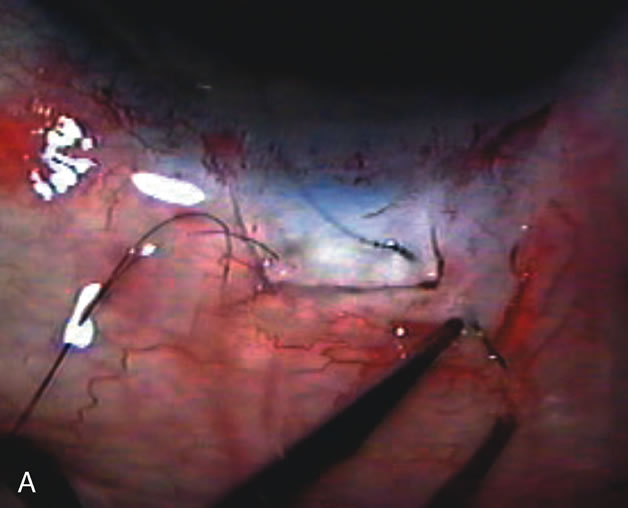

In years past, patients with both cataract and glaucoma frequently provided overwhelming surgical challenges for the ophthalmologist. The ability to carry out phacoemulsification through a 3.2-mm corneal incision along with inserting a foldable IOL is a vast improvement over 11-mm incisions that were common a decade ago (Fig. 1). The anatomical and inflammatory changes to the eye are less with small incision techniques, improving the likelihood of success with concomitant glaucoma surgery. Pharmacologic inhibition of fibrosis along with postoperative wound revision increases the long-term success rate of filtration surgery when combined with lens extraction. (Fig. 2). The learning curve may be steep at times, but the blending of cataract and glaucoma surgical skills slowly falls into place as the surgeon constantly learns and upgrades his or her technique.

Fig. 1. The anatomic advantage of small incision cataract surgery for the glaucoma patient. A. Long-term bleb function with a large cataract incision is difficult to achieve with either ECCE-trabeculectomy or trabeculectomy followed later by ECCE. This bleb failed to form sufficiently when combined with large incision ECCE. The inflammation, bleeding, and long-term wound healing with stimulation of fibroblasts associated with this technique are more likely to cause bleb failure. In addition, the increased iris manipulation necessary to deliver the nucleus and subsequent iris repair adds to the long-term breakdown of the blood aqueous barrier. B and C. Two-site phacotrabeculectomy has the advantage of small incision cataract surgery combined with separate site trabeculectomy. The incision size is one third the size of the standard ECCE. The inflammation is less severe, and cataract wound healing is confined to the temporal area. Visual rehabilitation with phacoemulsification and foldable IOL is much faster. Phacoemulsification allows successful lens extraction even in the unfriendly environment of a smaller pupil compared with ECCE. The trabeculectomy is performed in an entirely different site, well away from the wound healing associated with temporal phacoemulsification. The likelihood of this filter functioning long-term is greater than with ECCE-trabeculectomy. D. The surgeon also has the option of single-site phacotrabeculectomy with foldable IOL. Both the lens extraction and trabeculectomy are performed through one small 3.5-mm limbal incision.